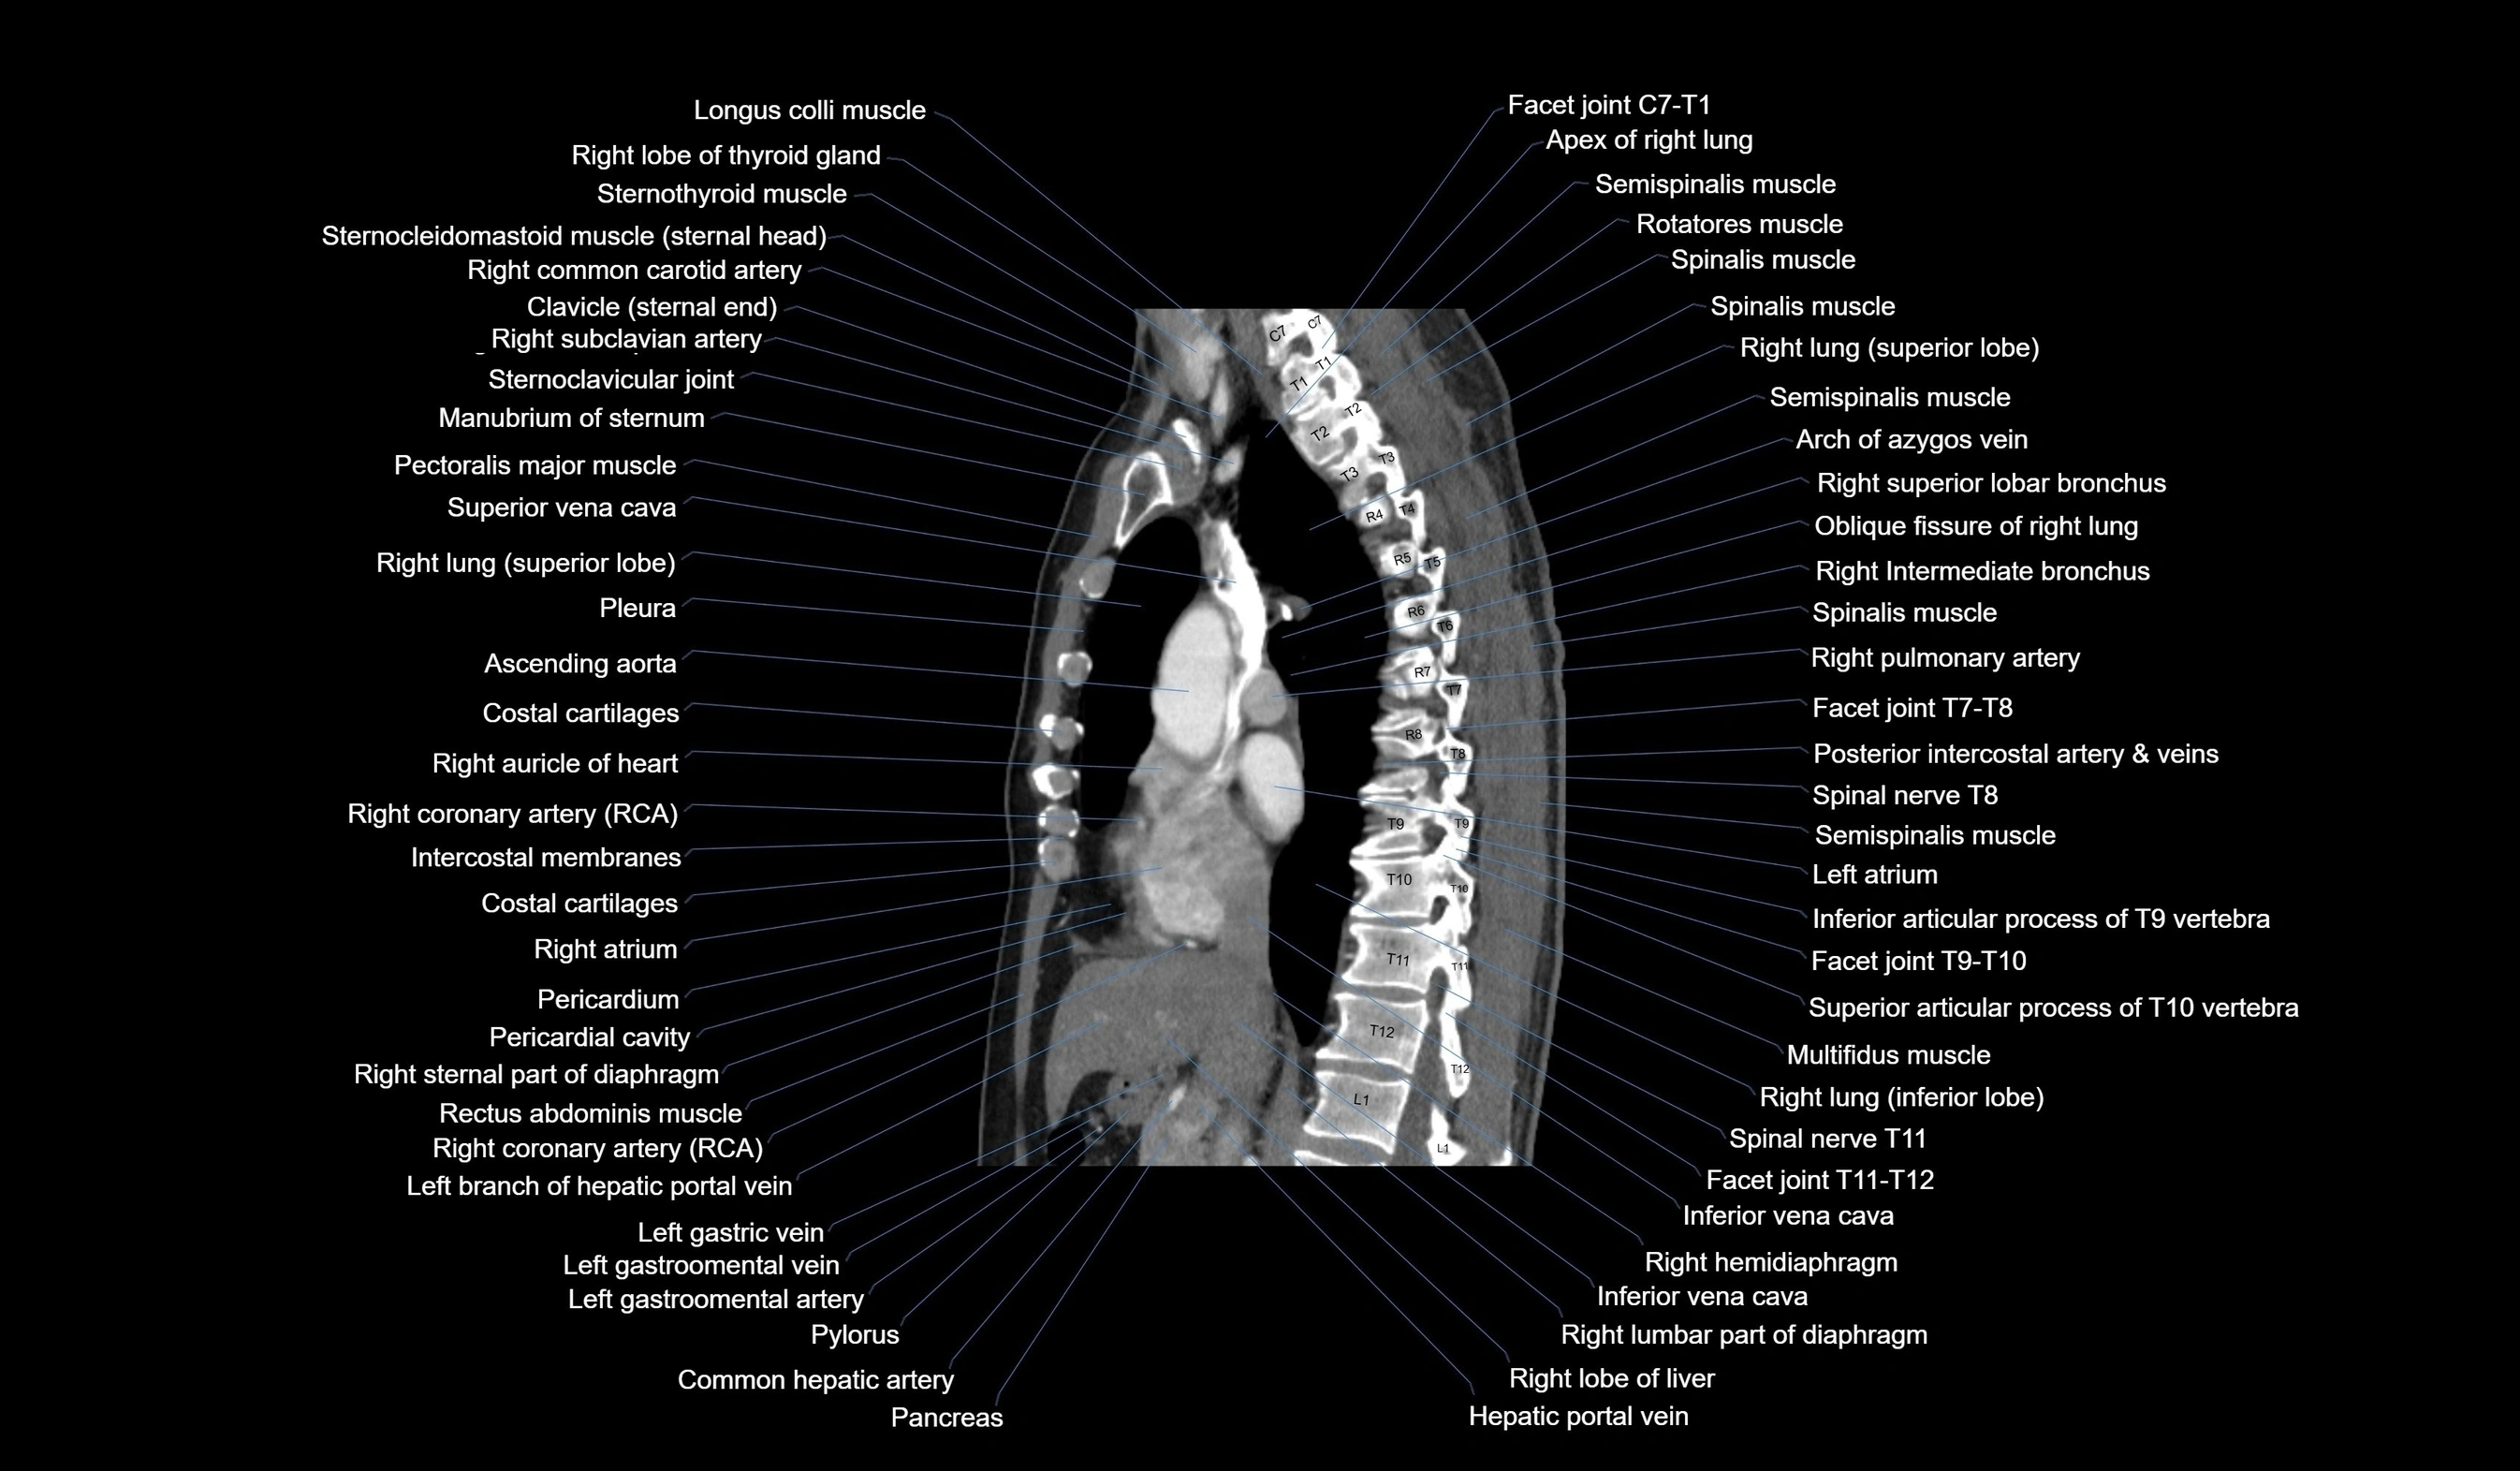

- T (Thoracic spine)

- Apex of right lung

- Right lung (superior lobe)

- Right lung (inferior lobe)

- Oblique fissure of right lung

- Azygos vein

- Right superior lobar bronchus

- Right intermediate bronchus

- Right pulmonary artery

- Right coronary artery (RCA)

- Right atrium

- Ascending aorta

- Descending thoracic aorta

- Inferior vena cava

- Hepatic portal vein

- Pancreas

- Common hepatic artery